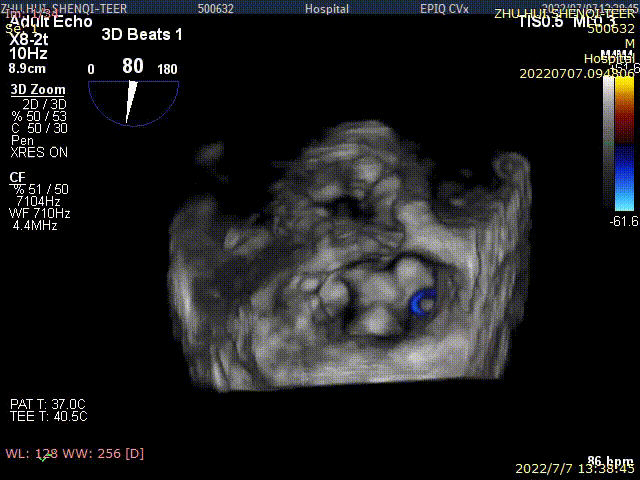

术后TEE显示,二尖瓣双孔化形成,反流明显减少